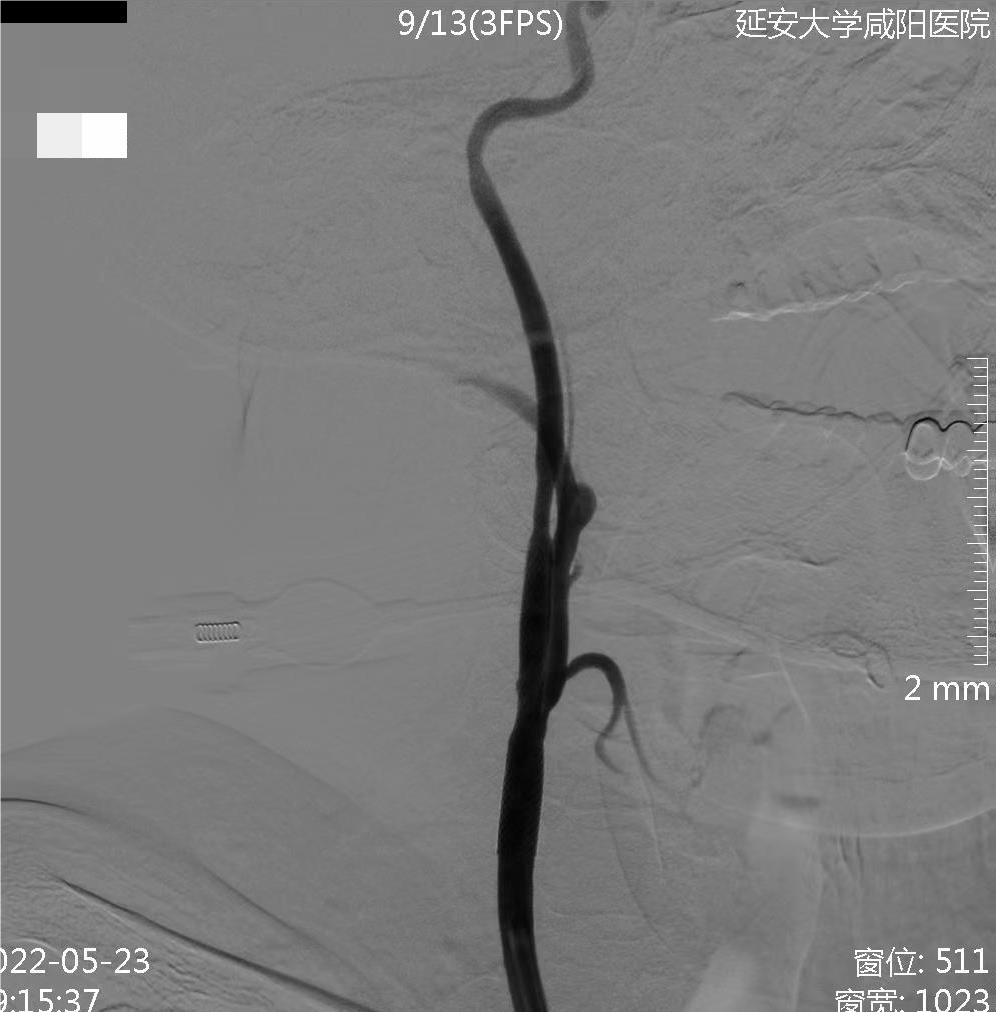

术前右侧椎动脉造影

病历夹什么径技·第152期|串联营病历夹:川陕大营_https://www.jmylbn.com_新闻资讯_第11张

病历夹什么径技·第152期|串联营病历夹:川陕大营_https://www.jmylbn.com_新闻资讯_第12张

病历夹什么径技·第152期|串联营病历夹:川陕大营_https://www.jmylbn.com_新闻资讯_第13张<<滑动查看下一张图片>>

术前左侧椎动脉造影

病历夹什么径技·第152期|串联营病历夹:川陕大营_https://www.jmylbn.com_新闻资讯_第14张

病历夹什么径技·第152期|串联营病历夹:川陕大营_https://www.jmylbn.com_新闻资讯_第15张

病历夹什么径技·第152期|串联营病历夹:川陕大营_https://www.jmylbn.com_新闻资讯_第16张

<<滑动查看下一张图片>>

左侧颈总动脉造影

病历夹什么径技·第152期|串联营病历夹:川陕大营_https://www.jmylbn.com_新闻资讯_第17张

右侧颈总动脉造影

病历夹什么径技·第152期|串联营病历夹:川陕大营_https://www.jmylbn.com_新闻资讯_第18张

病历夹什么径技·第152期|串联营病历夹:川陕大营_https://www.jmylbn.com_新闻资讯_第19张

病历夹什么径技·第152期|串联营病历夹:川陕大营_https://www.jmylbn.com_新闻资讯_第20张

左侧椎动脉起始部成形

病历夹什么径技·第152期|串联营病历夹:川陕大营_https://www.jmylbn.com_新闻资讯_第21张

病历夹什么径技·第152期|串联营病历夹:川陕大营_https://www.jmylbn.com_新闻资讯_第22张